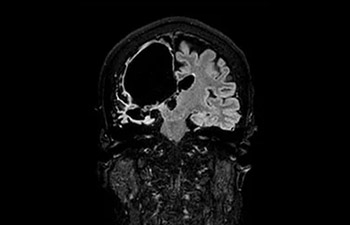

Hersenlaesie

met Compressed SENSE